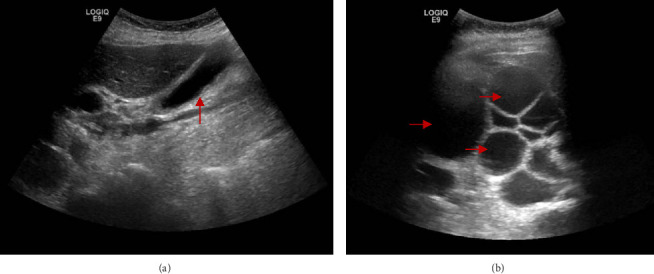

简介及重要性:囊性包虫病是流行地区常见的囊性感染。孤立性病变常见于肝脏,主要由细粒棘球绦虫引起。其他器官也可能受累,但程度较轻。本文报告一罕见的包虫性肝囊肿引起急性胰腺炎的表现。病例介绍:一名67岁女性,表现为右上腹疼痛、恶心和呕吐。她被发现有一个大的肝囊性包虫病占据肝脏右叶,并伴有急性胰腺炎。内窥镜逆行胆管造影(ERCP)后,发现三个小的黄色膜碎片(推测为子囊肿膜)阻塞了Vater壶腹处的胆总管。患者接受了腹腔镜下肝囊性包虫病开颅和腹腔镜胆囊切除术,术后过程平稳。临床讨论:肝囊性包虫病的治疗方式取决于囊肿的大小、影像学表现、囊肿活动状态和相关并发症。在非流行国家,由于来自流行地区的旅行而发生人口变化,因此需要高度的怀疑指数才能及时诊断。选择腹腔镜方法是因为其与微创手术相关的好处。虽然腹腔镜治疗肝囊性包虫病已有很好的报道,但其在急性胰腺炎合并病例中的应用仍然很少报道。结论:囊性包虫病最常见于肝脏。当合并急性胰腺炎时,通常需要阿苯达唑、ERCP和括约肌切开术联合入路,并根据囊肿分类进行手术切除。

Introduction and Importance: Cystic echinococcosis is a common cystic infection in endemic areas. Solitary lesions are commonly found in the liver and are primarily caused by Echinococcus granulosus. Other organs can be involved as well but to a lesser degree. This paper presents a rare manifestation of a hydatid liver cyst causing acute pancreatitis. Case Presentation: A 67-year-old female presented with right upper quadrant pain, nausea, and vomiting. She was found to have a large hepatic cystic echinococcosis occupying the right lobe of the liver with associated acute pancreatitis. After endoscopic retrograde cholangiopancreatography (ERCP), three small yellow membrane fragments-presumed to be daughter cyst membranes-were found obstructing the common bile duct at the ampulla of Vater. The patient underwent laparoscopic unroofing of the hepatic cystic echinococcosis and laparoscopic cholecystectomy with an uneventful postoperative course. Clinical Discussion: Treatment modalities for hepatic cystic echinococcosis depend on the size of the cyst, imaging findings, cyst activity status, and associated complications. In nonendemic countries, where demographic changes occur due to travel from endemic regions, a high index of suspicion is necessary for timely diagnosis. A laparoscopic approach was chosen for its benefits related to minimally invasive surgery. While laparoscopic management of hepatic cystic echinococcosis is well described, its use in cases complicated by acute pancreatitis remains infrequently reported. Conclusion: Cystic echinococcosis most commonly presents in the liver. When associated with acute pancreatitis, a combined approach involving albendazole, ERCP, and sphincterotomy is typically required, with surgical resection depending on cyst classification.